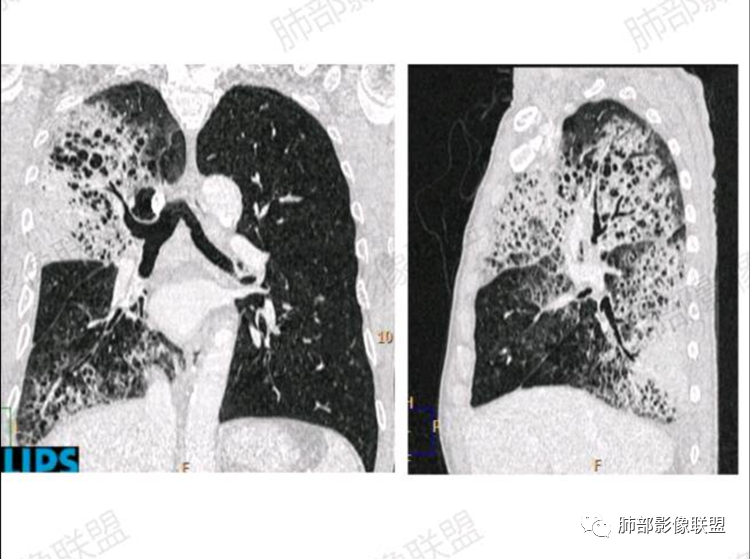

右肺体积缩小,右侧胸廓略塌陷,右肺中上叶多发簇状囊性影,大小不一,伴有间质增厚,胸膜下及脊柱旁多发实变影,宽基底与胸膜相连,平扫密度均匀,增强中等强化,左肺伴有散在斑片状磨玻璃影。

胸部CT:肺气肿,右肺上叶大片团片影,中叶纵隔侧小片影,下叶大片团片影;实变+磨玻璃+蜂窝,边界较清,小叶内间隔增厚,边缘膨隆为主,长轴平行于胸膜;实变区明显均匀强化,内部血管影稀疏。左肺上、下叶结节灶。老年病人,慢性病程,大量白色泡沫痰,肺部病灶重力分布、胸膜阻隔、左肺转移

4.左肺偶见小结节,但未见典型播散结节影。注意左肺未见蜂窝影。

5.纵隔轻度右移,提示右肺体积整体轻度减小。

1.单肺或单肺叶蜂窝样阴影(注意不是双肺对称性改变),切不可掉以轻心!尤其是病灶逐渐扩大进而出现实变时。

2.多病例的临床实践表明,如为新生物,以肺腺癌居多。希望有更多病例加以总结。